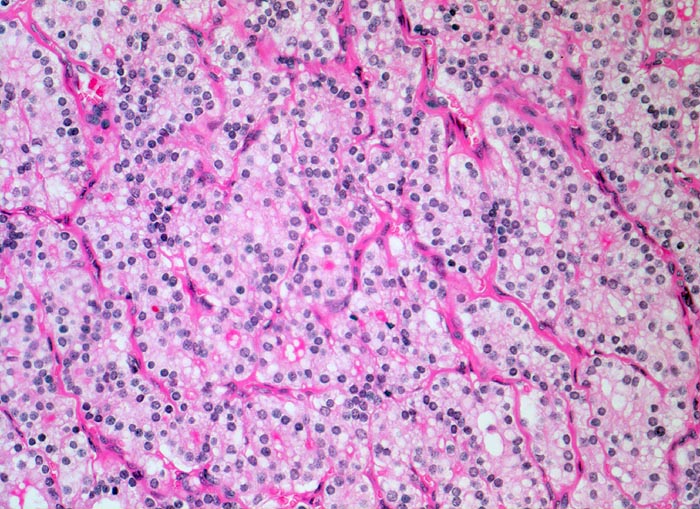

- Zeichen gesteigerter hormoneller Aktivität im Adenom:

- Kleine Drüsenlumina.

- Teils mehrreihiges kubisches bis zylindrisches Epithel.

- Fehlendes oder nur spärliches helles Kolloid mit zahlreichen Resorptionsvakuolen.